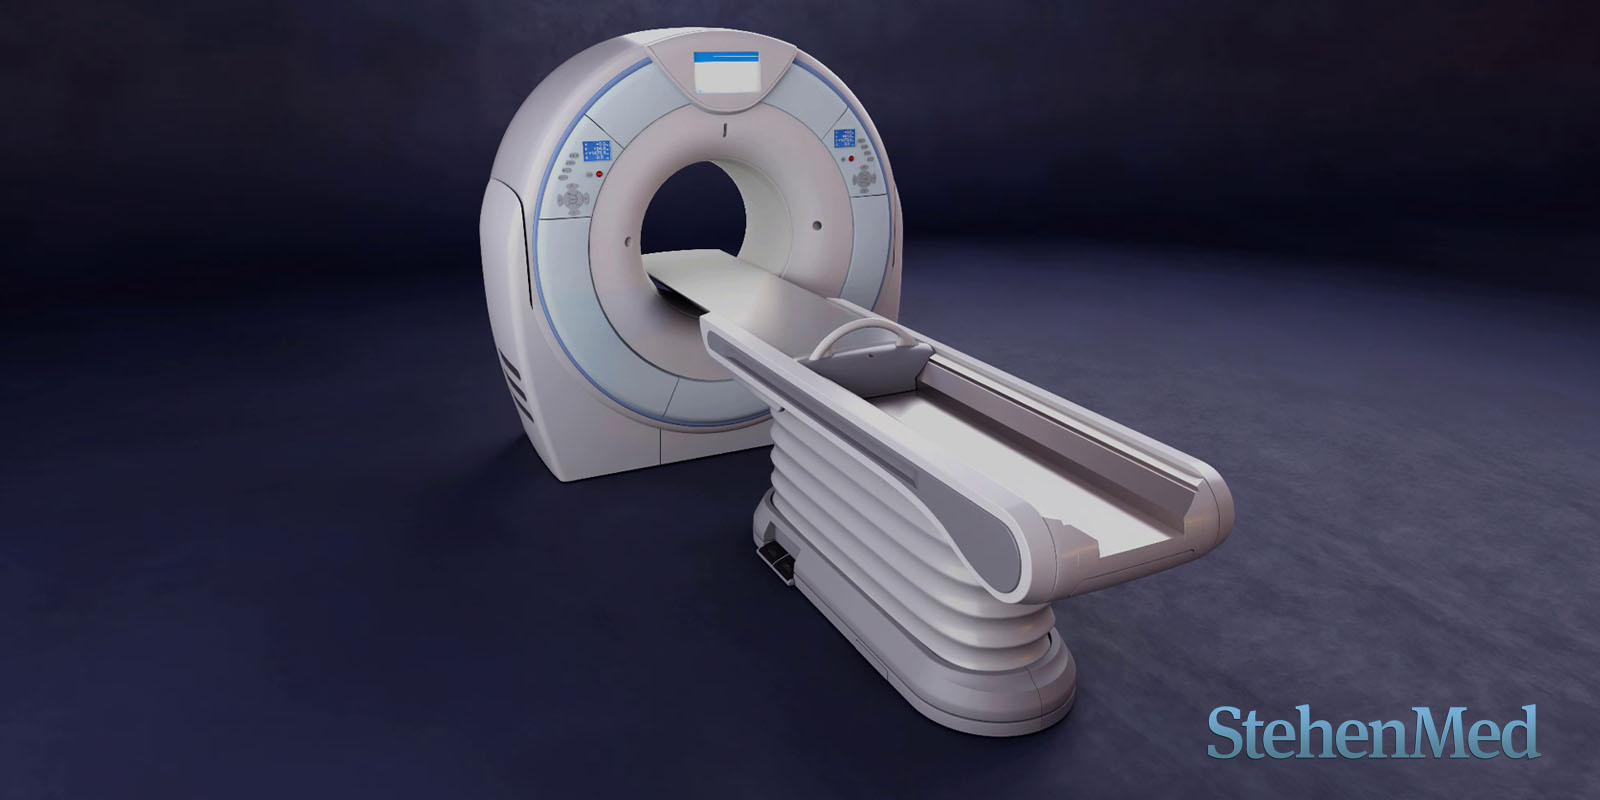

Modelado 3D de un CT Scanner y su camilla elevadiza

Categoría: Animación 3D - Render Producto

Conceptos clave: Render, CT Scanner, Producto

Duración: 1m 02s